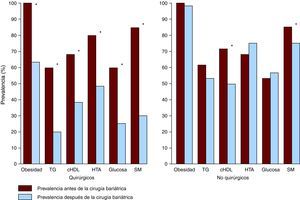

Cirugía bariátricaSe ha demostrado que la cirugía bariátrica es un método eficaz y seguro de pérdida de peso en pacientes con obesidad mórbida o con obesidad y comorbilidades, como la enfermedad coronaria87. Actualmente, existen principalmente dos técnicas operatorias para la cirugía bariátrica: la gastroplastia de banda vertical y el bypass gástrico en Y de Roux. Más de la mitad de los pacientes que se someten a cirugía bariátrica, especialmente los que se someten a bypass gástrico, pierden al menos el 50% del exceso de peso88. Algunos estudios indican que la cirugía bariátrica también puede inducir mejoras significativas en la presión arterial, la glucemia, las concentraciones lipídicas y la calidad de vida (Figura 5). Más del 70% de los pacientes con hipertensión notaron mejoría o resolución de los valores de presión arterial89. Cerca de la mitad de los pacientes diabéticos que se someten a cirugía bariátrica pueden normalizar la HbA1c e incluso pueden dejar de usar insulina o medicamentos hipoglucemiantes90. Los pacientes sometidos a cirugía bariátrica experimentan una reducción significativa en el riesgo cardiovascular estimado y algunos estudios indican disminución en la mortalidad después de la cirugía bariátrica91.

Figura 5. Cambios en la prevalencia del síndrome metabólico y en cada uno de los cinco componentes que lo definen, según la American Heart Association/National Heart, Lung and Blood Institute (AHA/NHLBI) después de cirugía bariátrica o después de intervenciones no quirúrgicas 90 . cHDL: colesterol unido a lipoproteínas de alta densidad; HTA: hipertensión arterial; SM: síndrome metabólico; TG: triglicéridos.*Cambios significativos (p<0,05).